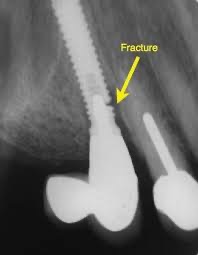

6️⃣ 植體鬆動(少見但最嚴重)

若植體本身與骨頭結合後受到過度咬力或感染,可能導致植體本體鬆動、斷裂。

這種情況通常需要重新評估、感染控制、甚至重新植牙。